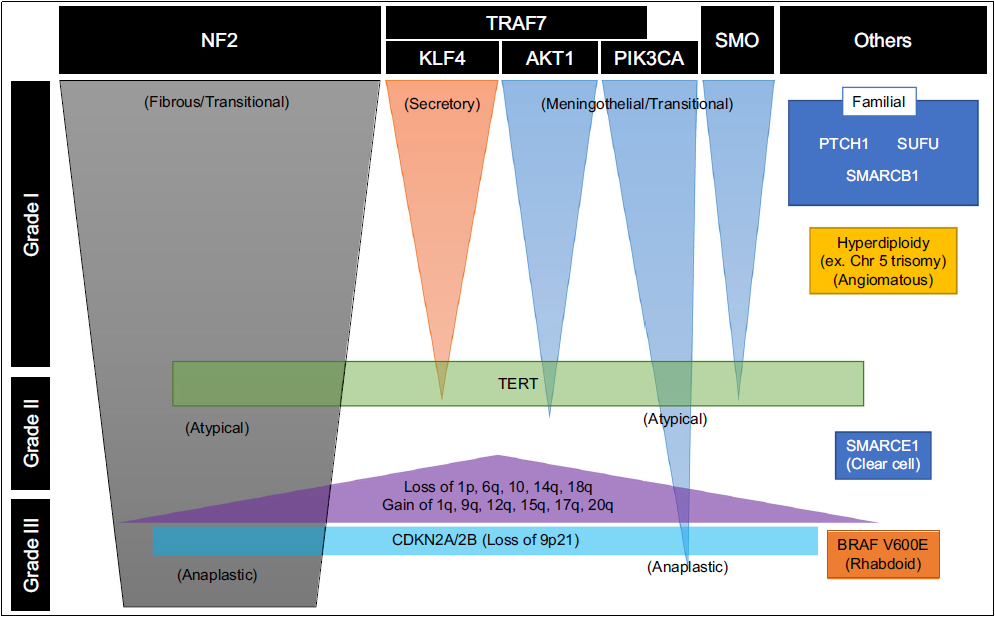

世界卫生组织(WHO)分类方案根据显微镜下的细胞类型将脑膜瘤分成15种组织亚型。这些组织学亚型分为三个等级(WHO I-III级),组织分型通常根据细胞学特征反映肿瘤生长速率和复发的可能性。非典型脑膜瘤(WHO II级,占脑膜瘤病例的18%)表现出组织和细胞异常增加。这些肿瘤的生长速度快于良性脑膜瘤,通常以脑部侵袭为特征。非典型脑膜瘤比良性脑膜瘤(WHO I级)复发的可能性更高。恶性脑膜瘤(WHO III级)显示细胞异常增加,并且比良性和非典型脑膜瘤的生长速度更快。恶性脑膜瘤比其他两种亚型更容易侵袭大脑并且复发频率更高。

癌症信号相关基因:研究者发现脑膜瘤中常常会有PI3K信号通路的相关基因突变,它们是AKT1和PIK3CA。研究表明这些基因的突变通常发生在WHOI级的脑膜瘤患者中。科学家还从脑膜瘤中鉴定到了SHH通路的相关基因突变,包括有PRKAR1A,SMO和SUFU。他们发现携带有SHH通路相关基因突变的脑膜瘤也属于WHOI的,且该类良性脑膜瘤进展复发的概率非常的小(Clark, Harmanci et al. 2016)。

脑膜瘤分子分型:脑膜瘤是常见的颅内原发性脑肿瘤,当前脑肿瘤的诊断模式是组织型和基因型的整合诊断。虽然目前脑膜瘤的诊断仍然引用传统的组织分型,但是分子检测在脑膜瘤瘤诊断和预后评估中的作用越来越大,尤其是检测复发相关的分子标志物。关于脑膜瘤分子分型的研究越来越趋于成熟,近期在柳叶刀肿瘤学期刊中发表了脑膜瘤6亚型的分子分型研究,其中恶性脑膜瘤通常携带有NF2,TERT基因启动子激活突变,CDKN2A基因缺失,1p和10号染色体缺失等分子特征。

阔然精准诊疗脑肿瘤产品CaptioX-M是一款以NGS技术为基础的检测产品。CaptioX-M用于脑膜瘤的分子诊断,涵盖了脑膜瘤复发相关的67个基因(NF2、TERTp、CDKN2A/B、ARID1A和BIP1等)、预后相关的染色体(22q、1p、5、10等)拷贝数变异和潜在靶向治疗相关基因的信息,脑膜瘤CaptioX-M可用于脑膜瘤患者分子分型、预后评估和辅助医生制定治疗策略。